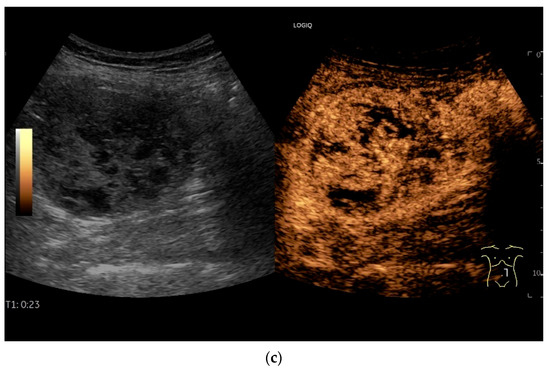

Figure 9.

Burkitt-Lymphoma. In a patient with weight loss, increased abdominal circumference, anemia, and physical weakness, the initial sonographic examination reveals an extensive tumor with intense hypoechogenicity and a connection to the jejunum in the left mid-abdomen. Despite its pronounced hypoechogenicity, a feeding vessel on CDI indicates a solid character (a). The tumor significantly thickens the wall and is intensely hypoechoic. The arrows point to the multisegmental hypoechoic wall thickenings (b). Normal wall structures are still visible (W), and the tumor extends beyond the wall (arrow) (c). In addition to delicate Kerckring folds (KF), there are significantly polypoid thickened KF with pronounced hypoechogenicity (d). The thickening of KF is very extensive (e). Wall thickening was found also in the stomach and colon and allowed endoscopic biopsy to establish the diagnosis.